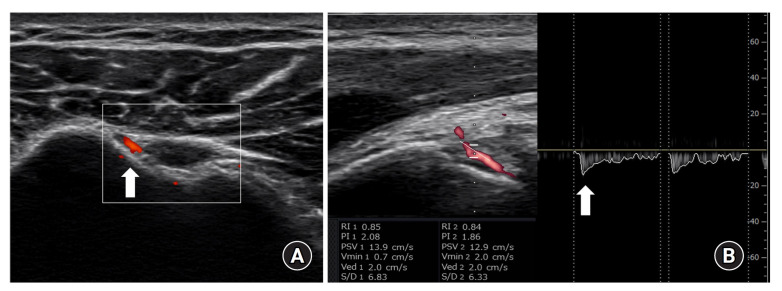

Methods: A total of 54 patients undergoing arthroscopic rotator cuff repair were selected. Doppler ultrasound was used to measure peak systolic velocity in the anterior humeral circumflex artery and Doppler activity in the glenohumeral joint and subacromial space, and these values were compared with the intraoperative synovitis score in univariate and multivariate analyses.

Results: Univariate analyses revealed that tear size, peak systolic velocity in the anterior humeral circumflex artery, and Doppler activity in the glenohumeral joint were associated with synovitis in the glenohumeral joint (P=0.02, P<0.001, P=0.02, respectively). In the subacromial space, tear size, peak systolic velocity in the anterior humeral circumflex artery, and Doppler activity in the subacromial space were associated with synovitis severity (P=0.02, P<0.001, P=0.02, respectively). Multivariate analyses indicated that tear size and peak systolic velocity in the anterior humeral circumflex artery were independently associated with synovitis scores in both the glenohumeral joint and the subacromial space (all P<0.05).